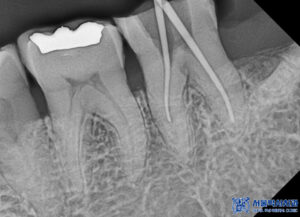

또한, 왼쪽 아래 치아는

맞닿는 위 치아의 상실로 인해

정출되어 교합을 방해할 수 있어,

신경치료 후 크라운 치료를 진행하였습니다.

이를 통해 치아의

기능을 회복하고,

교합을 정상화시킬 수

있었습니다.